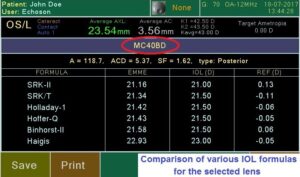

Современный ультразвуковой офтальмологический сканер для визуализации, биометрии и пахиметрии глаза.

Измерение параметров глаза и расчет ИОЛ.

Сенсорный экран (легкое использование благодаря понятному меню, виртуальная клавиатура для ввода данных пациента); внешняя USB клавиатура (опция), цветной 7″ LCD экран, 800×480 пикселей; десять (10) профилей пользователя; запись изображений на внешний USB накопитель; встроенный термопринтер; легкое обновление программного обеспечения через USB порт; USB порт для внешнего лазерного принтера; 6 типов отчета.